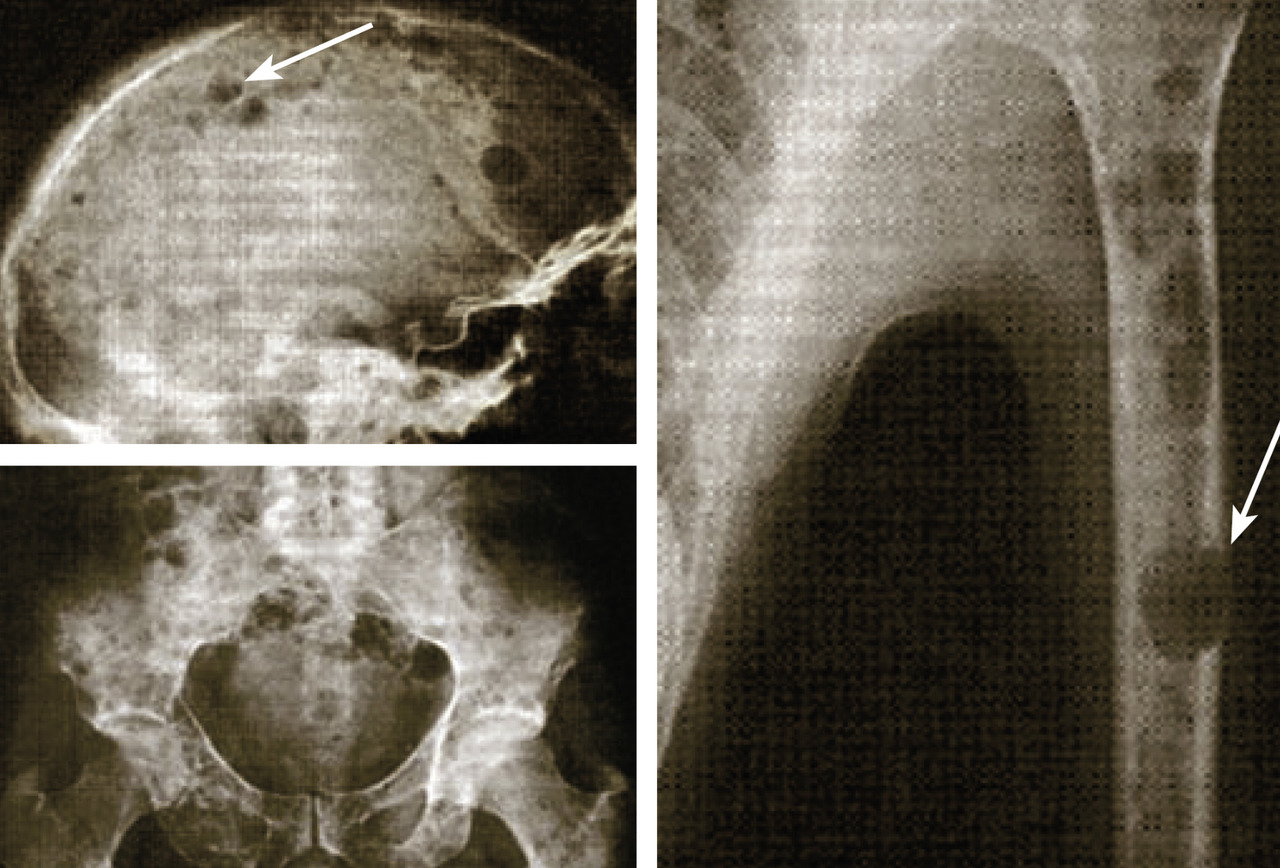

Imagerie du myélome

Les clichés standard du squelette axial (crâne, rachis, côtes et bassin) restent encore la référence pour diag­nostiquer une atteinte osseuse mais devraient être remplacés, en raison de leur faible sensibilité, par l’imagerie moderne. Les anomalies évocatrices sont une lyse à l’emporte-pièce (géode ou lacune), visible sur les os plats, associée ou non à une déminéralisation diffuse, ou sur les os longs avec résorption corticale et menace de fracture pathologique (fig. 4). Les lacunes peuvent être totalement asymptomatiques, notamment lorsqu’elles siègent sur le crâne. Les tassements vertébraux, plus ou moins complets, voire en galette, sont toujours symptomatiques. Le scanner du corps entier faible dose devrait remplacer les clichés standard en raison de sa plus grande sensibilité, de sa durée de réalisation plus courte et de sa plus faible dose délivrée d’irradiation. L’IRM du corps entier et le TEP-scan détectent 20 % de lésions supplémentaires par rapport aux clichés osseux standard sous la forme d’images nodulaires en hyposignal T1 et hypersignal T2 et STIR, pour l’IRM (fig. 5), ou de foyers hypermétaboliques correspondant aux lacunes sur le scanner, pour le TEP-scan (fig. 6). Ces examens sont particulièrement utiles dans les formes peu avancées de la maladie (absence d’anomalie sur les clichés standard), pour dépister une épidurite ou confirmer le caractère tumoral du tassement vertébral (IRM) et pour suivre l’évolution sous traitement (réponse métabolique au TEP-scan avec disparition des foyers hypermétaboliques). Leur utilisation est en cours de validation et limitée par leur accessibilité.